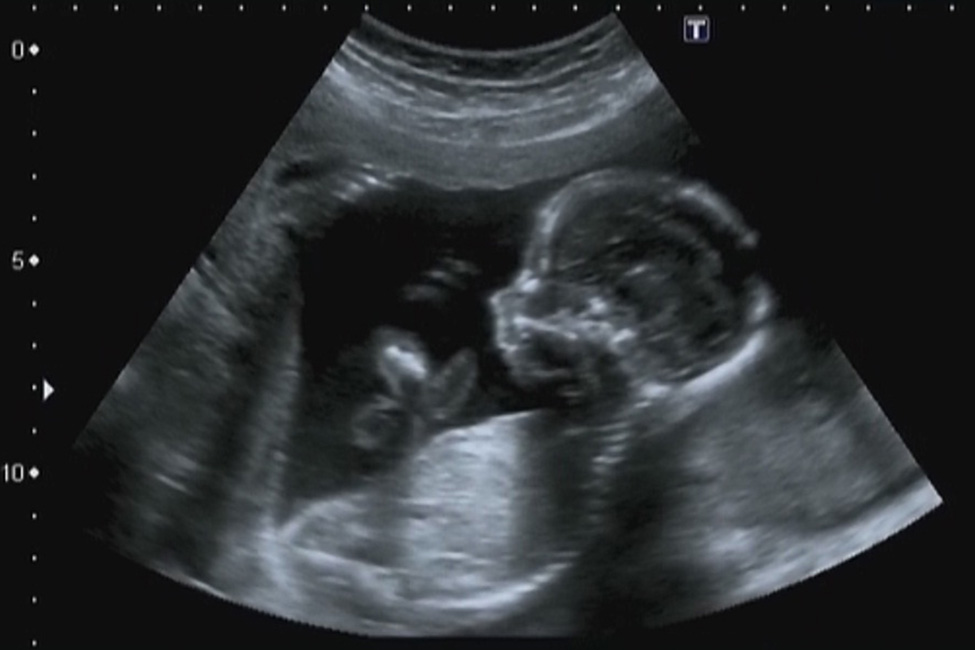

Pregnancy Ultrasound

Please select your required scan below...

Ultrasound In Early Pregnancy

Sexing Scan